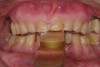

Figure 3  Preoperative view. Note the worn incisal edges and end-on-end occlusal relationship requiring an increase in OVD to restore.

Figure 3

The registration of the transverse hinge axis and transfer with a facebow simply serves to locate the maxillary cast on the articulator. An accurate registration of centric relation allows the laboratory to mount the mandibular cast in a repeatable position for the purposes of reconstruction.18 Commonly, interocclusal records provided to the laboratory are with teeth in contact or the laboratory is asked to hand-articulate without the benefit of a bite registration. Besides a lack of repeatability, casts mounted in contact must be separated to a working vertical dimension. Because the earbow/facebow mounting is an arbitrary positioning of the maxilla, the casts will routinely not be on the same arc of closure as found intraorally. This means that as the casts are separated there is the possibility of a significant anterior–posterior shift.19 The error compounds the farther from the true hinge axis the facebow was fabricated and the greater the casts are opened on the arbitrary arc. Because of this magnifying error, Gracis suggests that interocclusal records should be fabricated at the vertical dimension that they will be rehabilitated.19 Dentists should visualize the ideal incisal edge position of the maxillary incisors and their ability to couple at the proposed vertical. Evaluating the patient’s central incisor display in repose and full smile arrives at this position.17 The author then uses a leaf gauge to separate the anterior teeth enough to accommodate the additional length (Figure 3 through Figure 5). The leaf gauge has the additional benefit of allowing the interocclusal registration to be fabricated with a seated condyle. This is obviously an arbitrary choice. The laboratory technician will alter the position during the diagnostic wax-up. Due to the fact that the registration is fabricated in an open relationship, the amount of modification in the OVD on the articulator will be significantly less. This will minimize the error found in wax-ups fabricated from a closed interocclusal record.